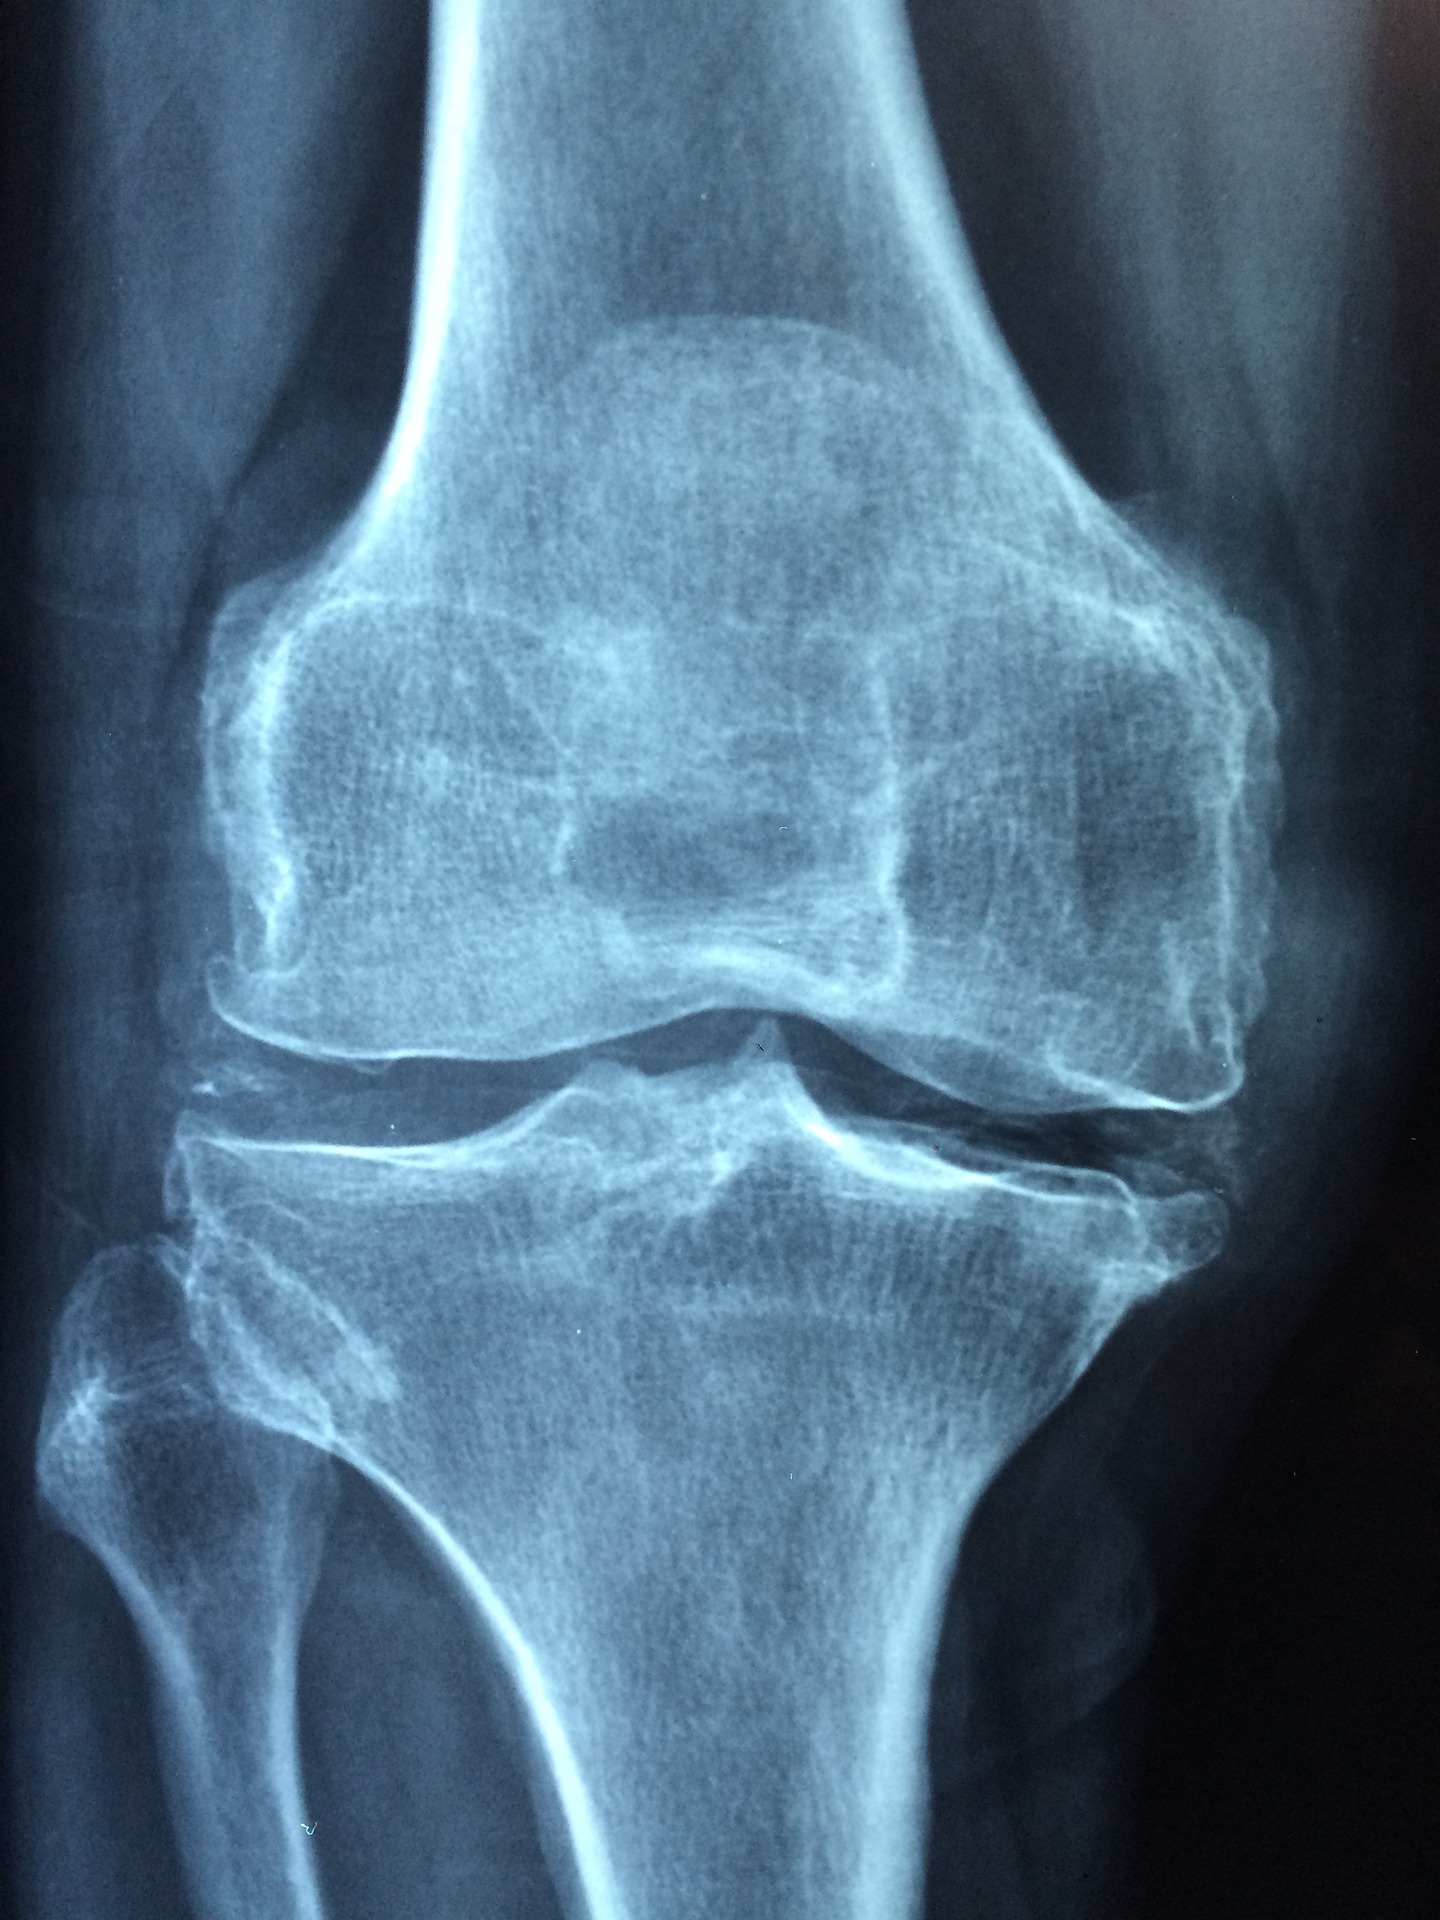

2. 관절염

대부분의 관절염 환자는 다리 또는 팔의 부위가 관절염에 가장 많이 호소합니다. 그러나 오른쪽 옆구리는 관절염이 있는 경우 아픈 경우가 생길 수 있습니다. 그 이유는 다음과 같습니다.

첫째, 오른쪽 옆구리는 다리보다는 가벼운 부위이기 때문에 오른쪽 옆구리의 관절이 스트레스를 받기 쉽게 됩니다. 관절염이 있는 경우 이러한 스트레스가 관절내에 쌓이게 되어 오른쪽 옆구리를 가려 아픔을 느낄 수 있게 됩니다.

둘째, 오른쪽 옆구리는 일상생활 중 운동을 잦게 하는 부위이기 때문에 관절염이 있는 경우 이 부위에 더 많은 스트레스를 줄 수 있기 때문에 오른쪽 옆구리가 아픈 경우가 발생합니다.